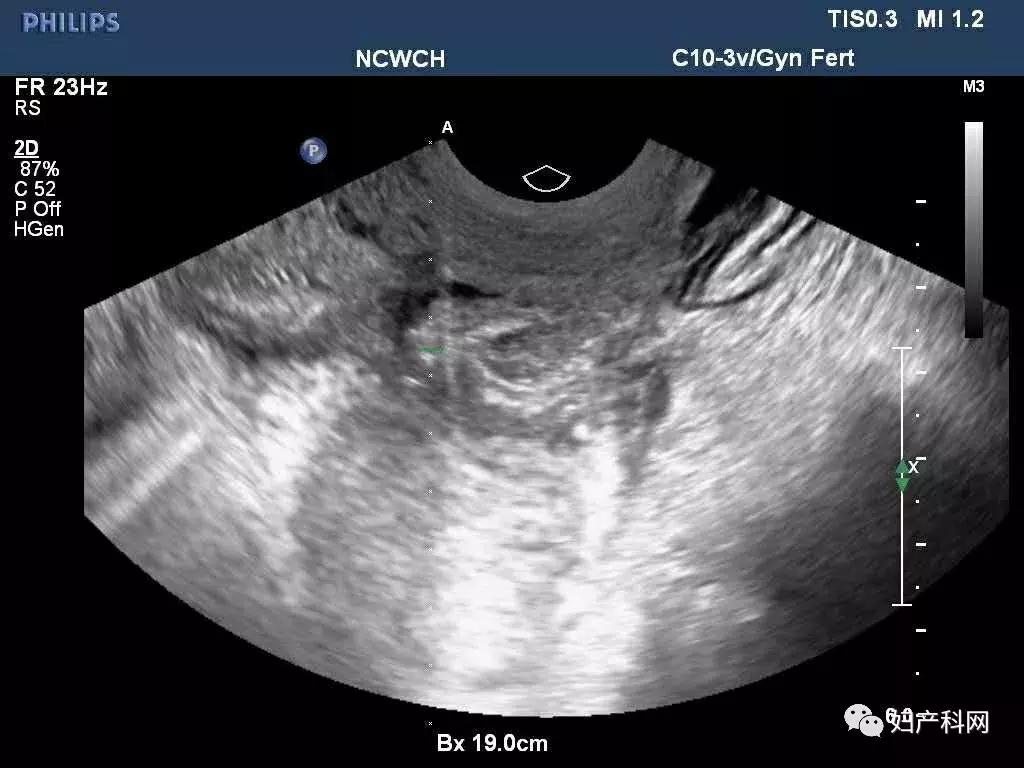

超声提示:右侧卵巢囊肿大小约7.4×4.7cm,巧囊不除外,ca125 37.7u/ml,HE4 40.6pmol/L。

术中超声

我们给这位患者选择的是经阴道卵巢囊肿穿刺+无水酒精固化,术中见右侧卵巢囊肿分为2房,分别从2房中抽出了约100ml巧克力样粘稠液体,共计200ml,每个房分别注入了50ml的无水酒精固化15分钟后抽出,术中同时放置了一枚曼月乐。

前几天这位患者再次来我们门诊复查,之前因为卵巢囊肿过大,超声甚至很难找到右侧正常卵巢组织,这一次可以轻松的发现了,囊肿也没有复发,当然后续还需要进行持续的随访。